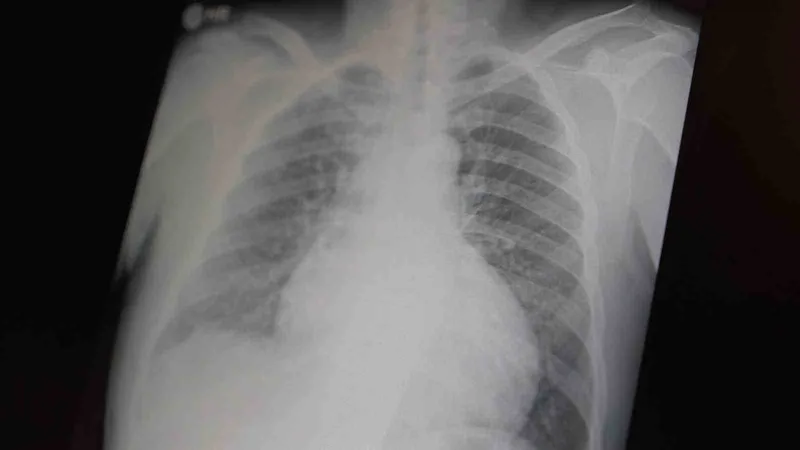

Göğüs Hastalıkları Uzm. Prof. Dr. Şevket Özkaya, tüm dünyada çocuk ve gençleri etkileyen iki önemli bağımlılığın metamfetamin ve kokain olduğunu belirterek, her iki uyuşturucunun ciddi sağlık sorunlarına ve ölümlere yol açtığını açıkladı.

Prof. Dr. Şevket Özkaya, çocukları ve gençleri etkileyen bağımlılıklar hakkında açıklamalarda bulundu. Metamfetaminin sentetik bir uyuşturucu olduğunu ve kullanımının ölümcül sonuçlar doğurduğunu ifade eden Özkaya, "Tüm dünyada çocukları ve gençleri etkileyen iki önemli bağımlılıktan bahsetmek istiyorum. Bunlar metamfetamin ve kokain bağımlılığıdır. Metamfetamin en ölümcül, en çok bağımlılık yapan, okul çağında en kolay ulaşılabilen bir sentetik uyuşturucudur. Kullanıma bağlı ciddi akciğer ve karaciğer sorunları ortaya çıkıyor. Çok küçük dozlarda bile anında bağımlılık yapabiliyor ve tedaviyle bırakılması çok zor bir bağımlılıktır" dedi.

Açıklamalarında, her iki uyuşturucunun beyin hasarı oluşturduğunu ve nöro sinir hücrelerini harap ederek solunum ve kalbin durmasına sebep olduğunu vurgulayan Özkaya, "Metamfetamin tüm dünyada bir sorun olmanın ötesinde, ülkemizde de gençlerimizi etkileyen toplumsal bir sorun olarak görülmelidir" ifadelerini kullandı.